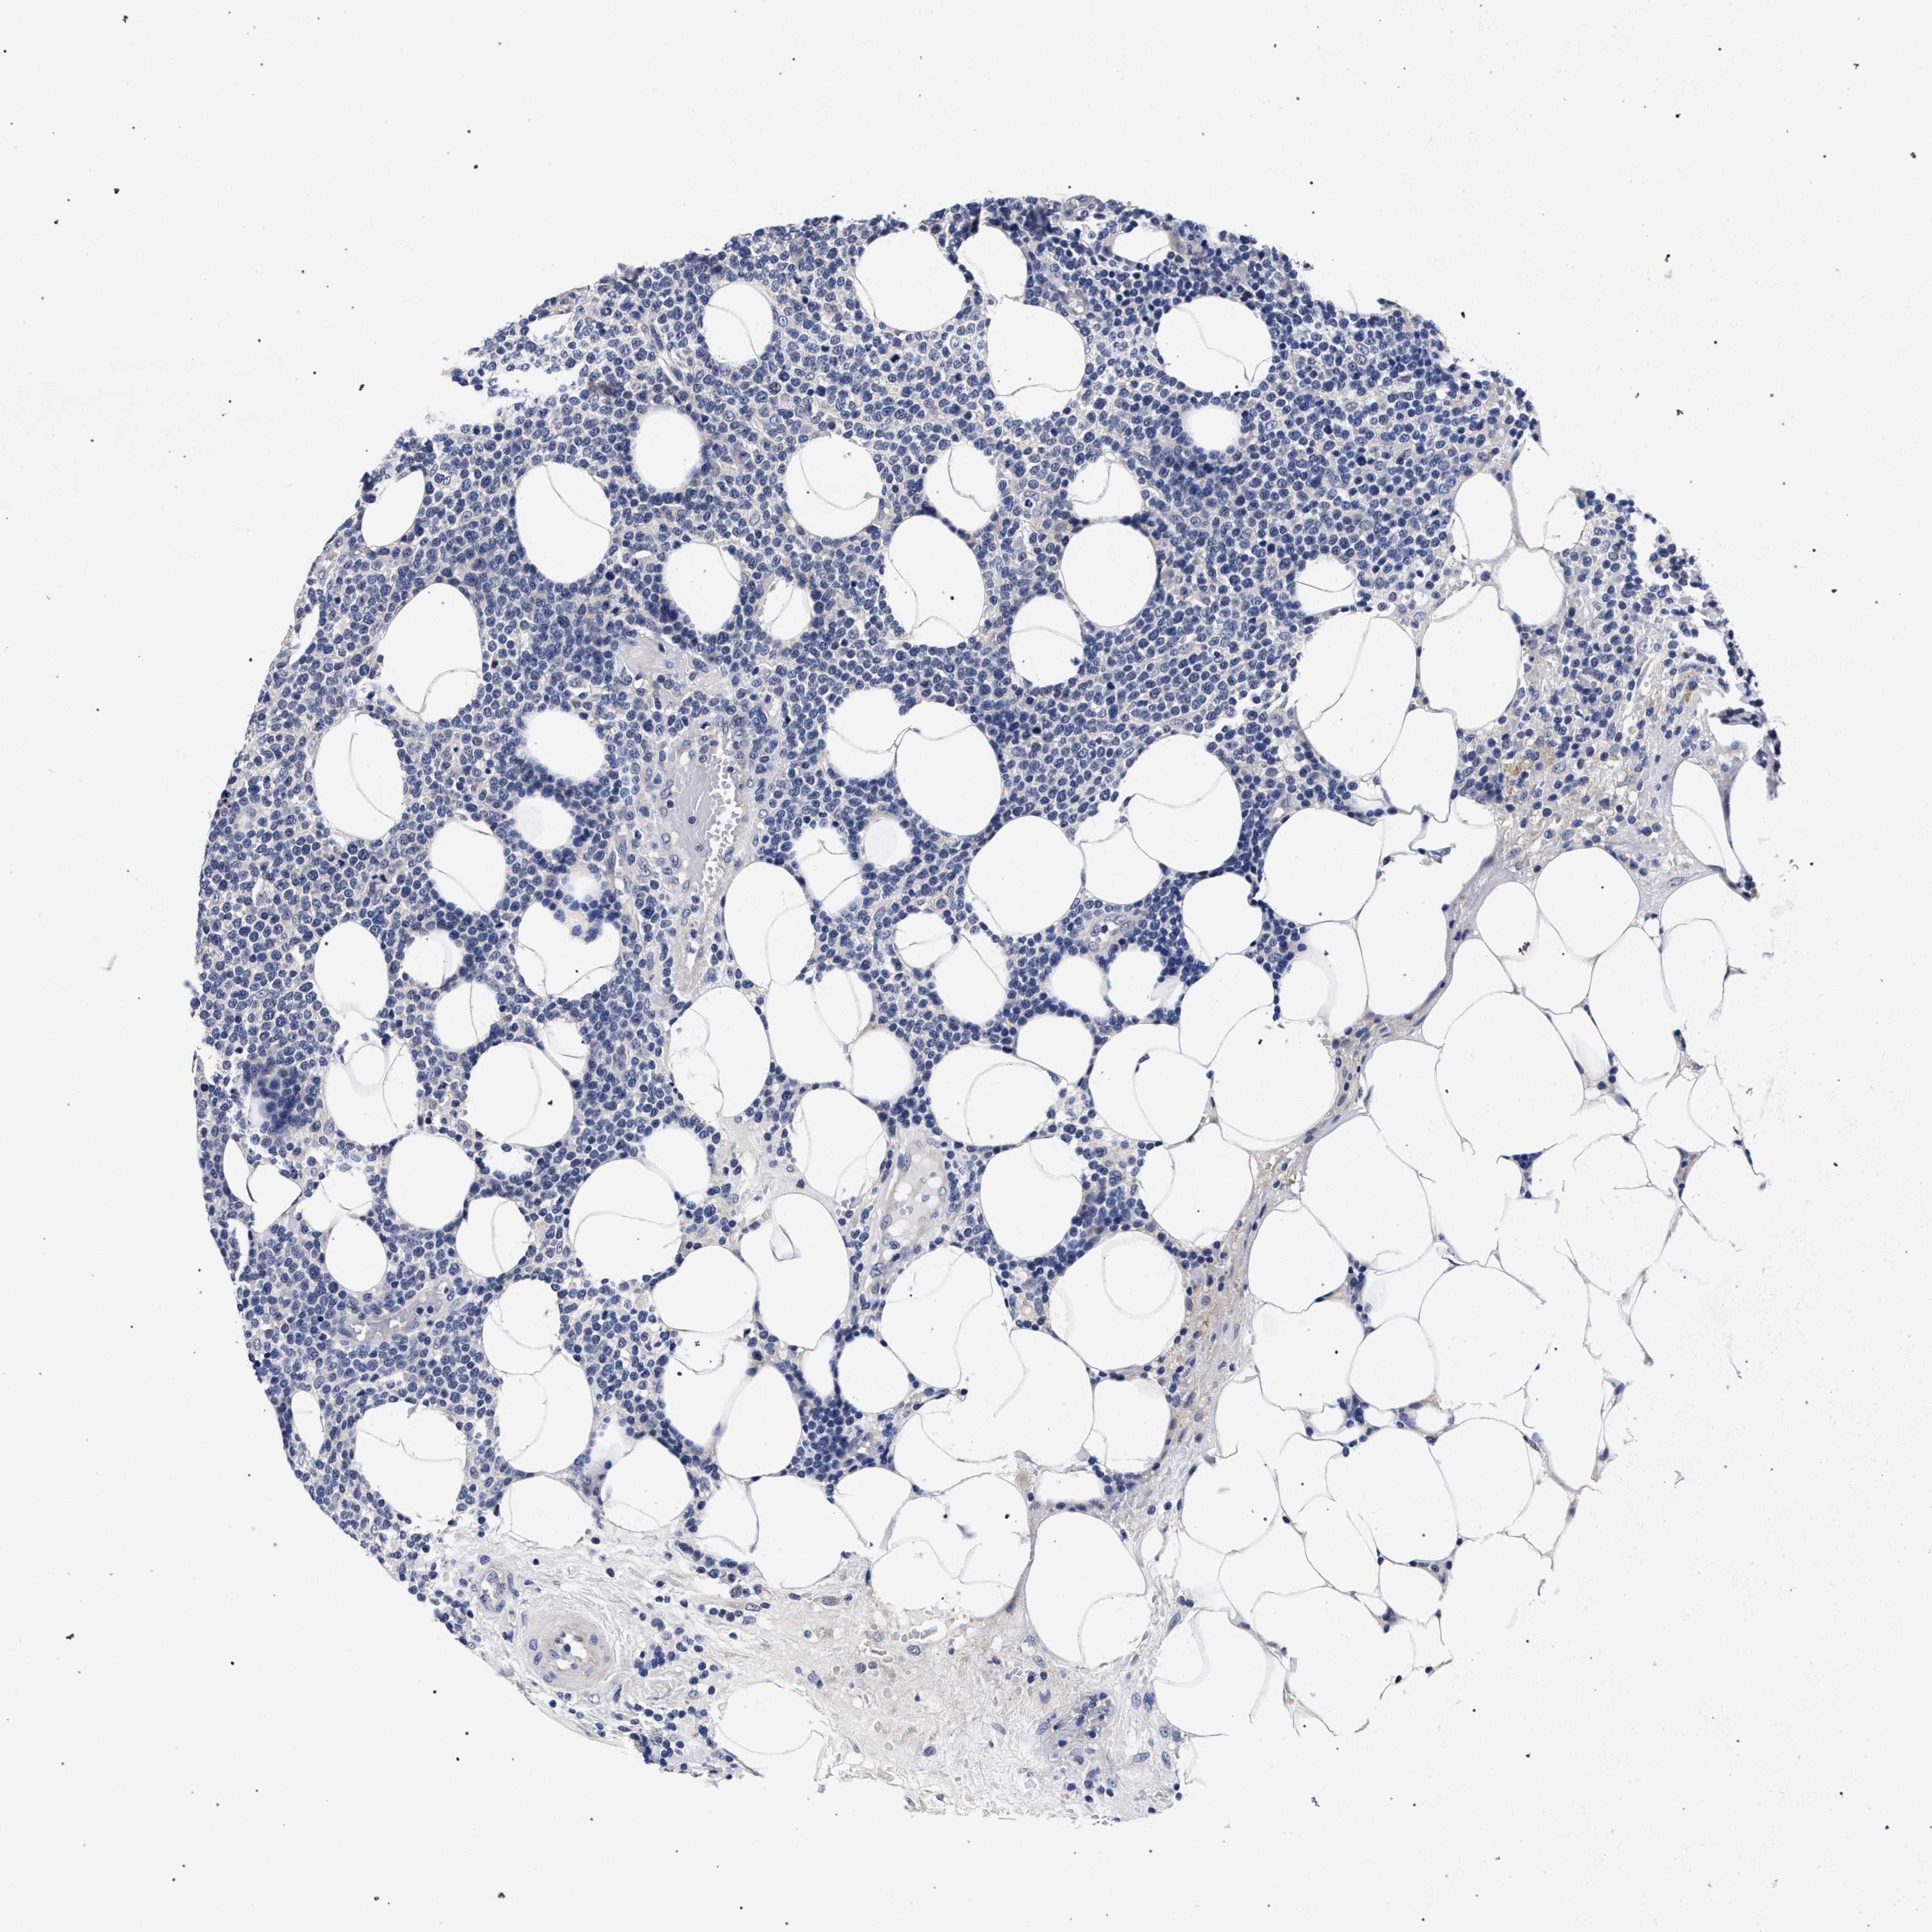

LYMPHOMA - Protein expressioni

A mouse-over function shows sample information and annotation data. Click on an image to view it in a full screen mode. Samples can be filtered based on level of antibody staining by selecting one or several of the following categories: high, medium, low and not detected. The assay and annotation is described here.

Each image is clickable and will lead to virtual microscopy that enables deeper exploration of all samples and also displays staining intensity scores, fraction scores and subcellular localization as well as patient and tissue information for each sample.

Hodgkin's disease, NOS

Malignant lymphoma, non-Hodgkin's type, High grade

Malignant lymphoma, non-Hodgkin's type, Low grade